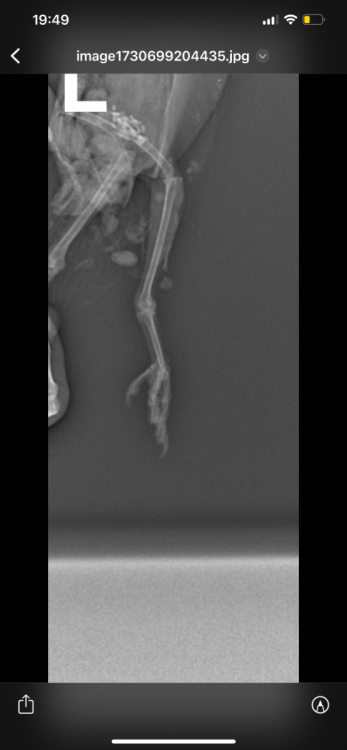

Здравствуйте, неделю назад возле автомобиля обнаружила голубя , лежал на левом боку и не мог встать. Я подумала что сбила машина, взяла его к себе. Съездили к орнитологу , он пощупал лапки , сказал возможно это связано с нервной системой , либо повреждена левая лапа. Голубь, взлетает без проблем. Но не упирается на лапы , теряет координацию и падает + постоянно вся попа в 💩. Кушает хорошо и пьет водичку самостоятельно. Сегодня смотрю , упирается на правую лапу , а левую вытягивает прямо назад.

На всякий случай купила витамины, добавляю по капельки в водичку. Голову не запрокидывает.  Фото рентгена прилагаю. Кто сталкивался с подобным ? Что может быть ?

Возможно есть повреждение бедренной кости- выбита или перелом головки.